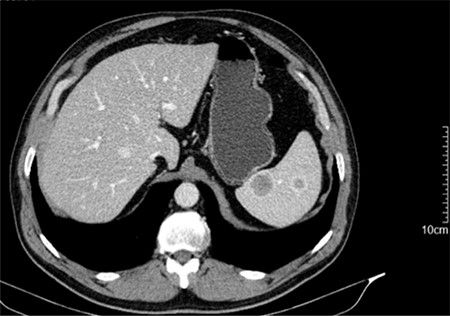

In order to clarify the US findings, an abdominal CT scan was obtained (Fig. 1), which revealed five ring-enhancing nodular lesions 27, 20, 18, 11 and 10 mm in diameter, not clear whether they represent benign or malignant secondary lesions.

CT scan showing two of the five ring-enhancing nodular lesions.